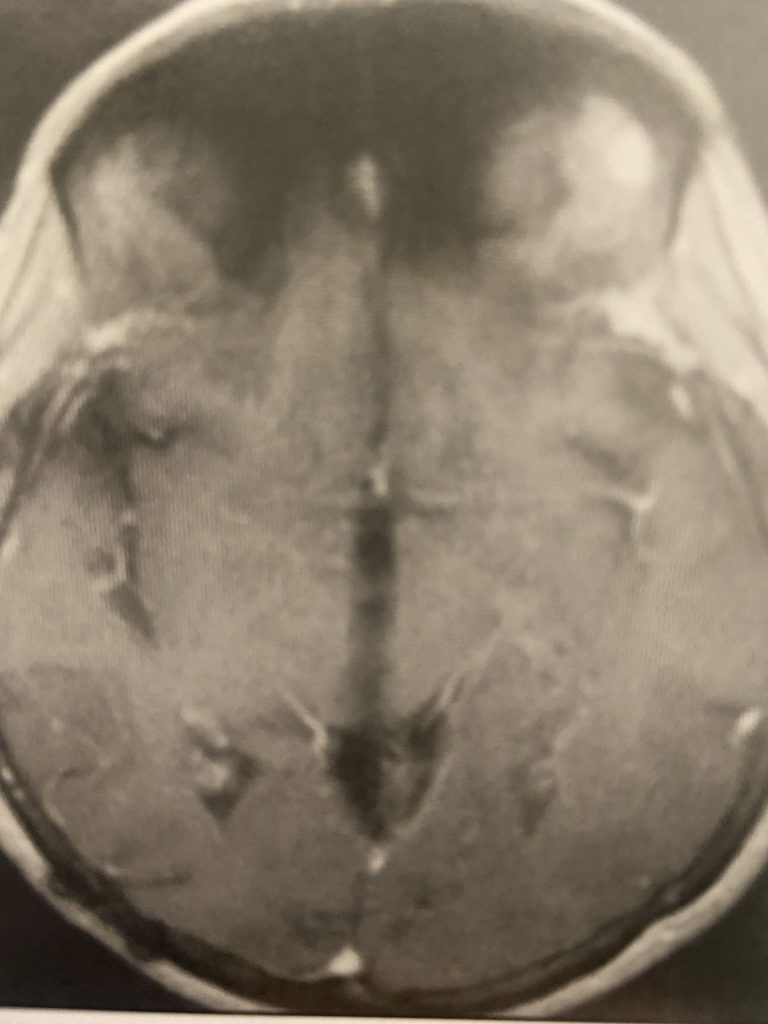

Subsequently, the hydrocephalus resolved and the patient did not require shunting. Her pre-operative symptoms all resolved. Follow up MRI demonstrated complete removal of the tumor.

Figure 3

Figure 4

Postoperative post contrast axial MRIs demonstrating complete removal of the tumor with resolution of the hydrocephalus.

Surgery in this case was uneventful and led to a complete removal of the tumor, and resolution of the hydrocephalus and all pre-operative symptoms.